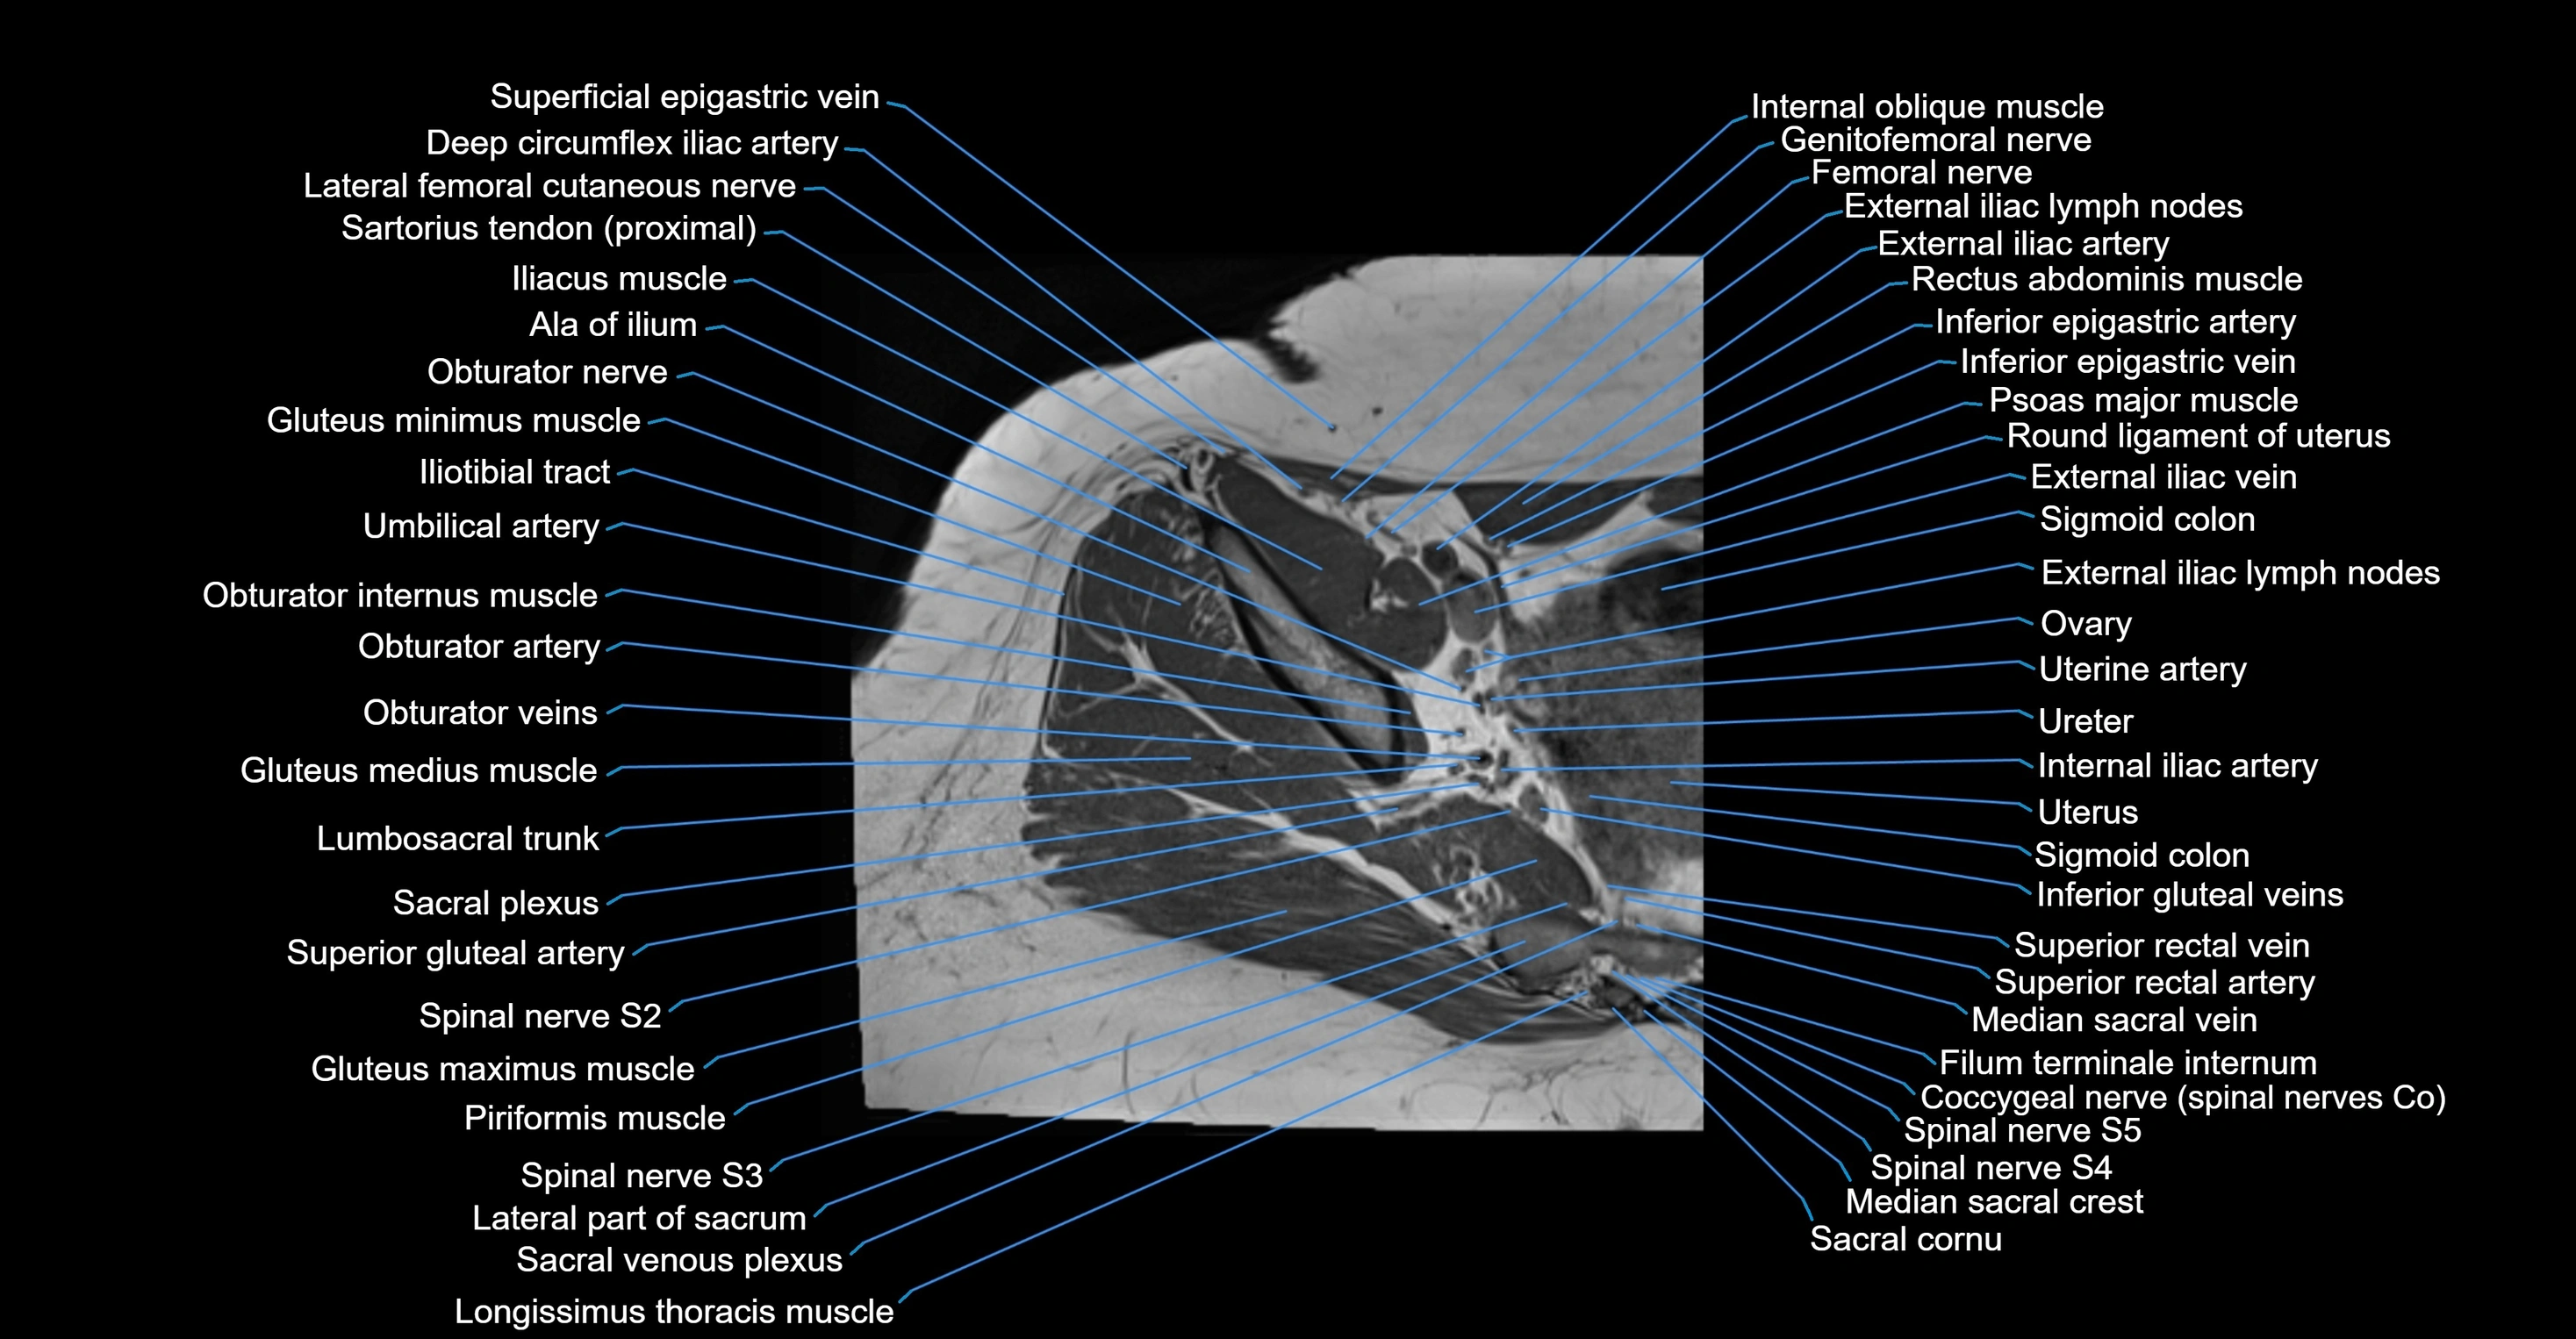

- Ala of ilium (wing of ilium)

- Deep circumflex iliac artery

- External iliac artery

- External iliac lymph nodes

- External iliac vein

- Femoral nerve

- Genitofemoral nerve

- Gluteus medius muscle

- Gluteus minimus muscle

- Iliotibial tract

- Ilium bone

- Internal iliac artery

- Lumbosacral trunk

- Median sacral vein

- Obturator artery

- Obturator internus muscle

- Obturator nerve

- Obturator veins

- Psoas major muscle

- Round ligament of uterus

- Sacral plexus

- Sigmoid colon

- Spinal nerve S2

- Spinal nerve S3

- Spinal nerve S4

- Spinal nerve S5

- Superior gluteal artery

- Superior rectal vein

- Superior vesical artery

- Umbilical artery

- Uterine artery

- Uterus